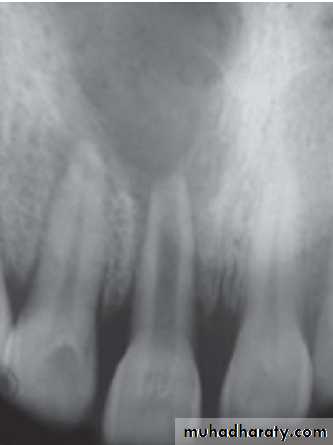

6) Internal root resorption Internal resorption is initiated within the pulp cavity and results in loss of substance from dentinal tissue.EtiologyExact etiology is unknown. Patient often presents with history of trauma, persistent chronic pulpitis, history of pulpotomy, crown preparation, force from orthodontic treatment, impacted teeth,…etc.

Symptoms

• Usually asymptomatic, recognized clinically through routine radiograph (especially in the root)• Pain occurs in cases of perforation of crown.

• “Pink Tooth” is the pathognomic feature of internal root resorption (especially in the crown).

Diagnosis

• Clinically:“Pink Tooth” appearance

• Radiographic changes:

– Radiolucent enlargement of pulp canal

– Original root canal outline distorted

– Bone changes are seen only when root perforation into periodontal ligament takes place.

• Pulp tests: Positive, though coronal portion of pulp is necrotic, apical pulp could be vital

Treatment

• Pulp extirpation stops internal root resorption.

• Surgical treatment is indicated if conventional treatment fails.